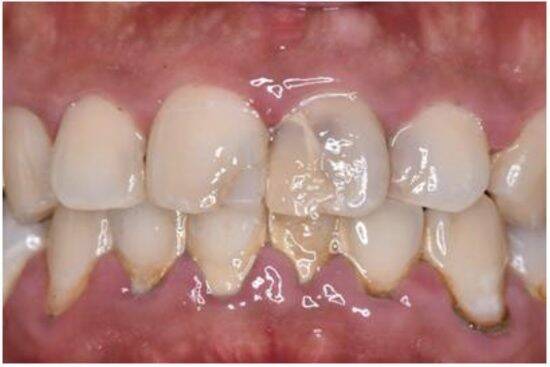

・黄ばんだ歯

・歯並びの乱れ

・歯茎が不健康

これらはすべて「だらしない」「自己管理ができない」という印象につながります。営業、接客、管理職、メディアに出る仕事ほど、口元の印象=評価と言っても過言ではありません。

例えば、営業に来た人が口臭が強く、黄ばんだ歯に、不健康な赤黒い歯茎だったらみなさんはその商品やサービスを取り入れようとはなかなか思えないはずです。人は、7秒以内に、この人から買うかを無意識に決めているからだと言われています。